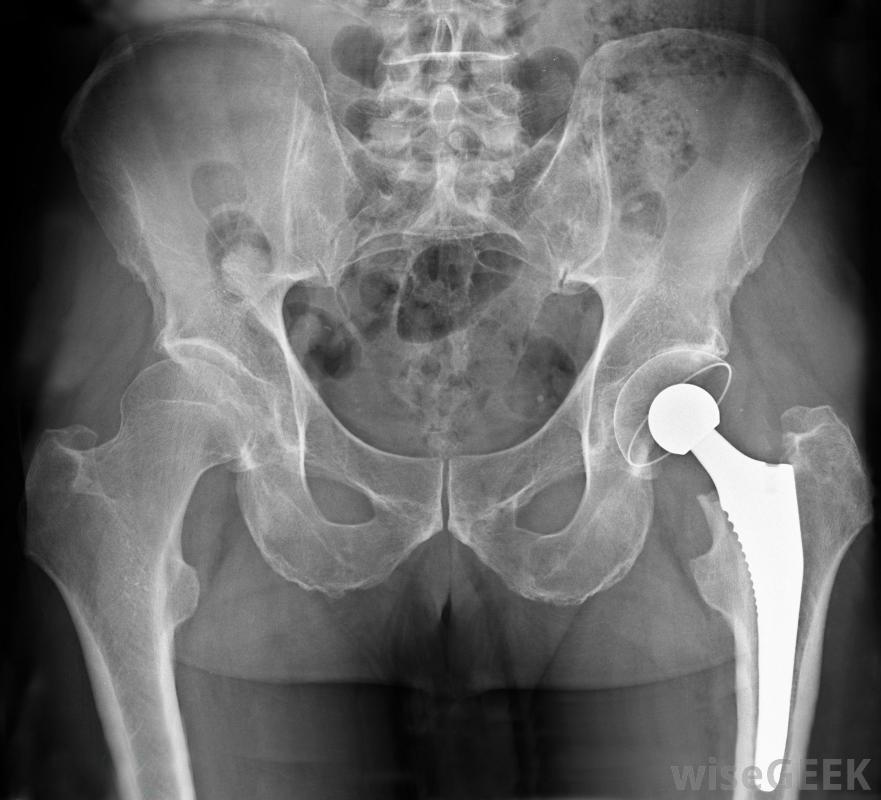

骨盆区域的X光片,显示髋关节置换术采用这种方法,患者住院时间通常较短,康复时间也较短。在传统的髋关节置换手术中,肌肉和肌腱被切断,以便从髋关节外侧进入并替换髋关节。这可能导致住院时间更长,以恢复从手术中然而,在前入路髋关节置换术中,参与髋关节功能的肌肉是单独存在的,这意味着患者在手术后立即可以在髋关节处正常弯曲。在其他类型的髋关节置换手术中,在恢复期,髋关节的运动和活动范围有许多限制